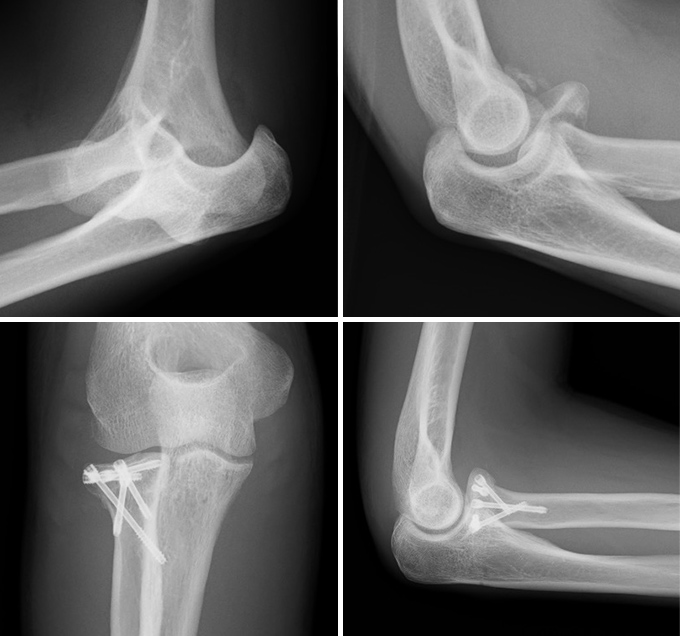

上腕骨遠位端骨折

肘を構成する上腕骨の末端が折れる外傷で、転倒や交通事故などで強い衝撃が加わって発生します。関節面のずれや骨片の転位を伴うと、肘の安定性と可動域が大きく損なわれます。治療の基本は、プレートやスクリューによる解剖学的整復と強固な固定であり、手術後は早期からリハビリを開始して肘の動きを保つことが極めて重要です。高齢者では骨の脆弱性や全身状態に応じて、保存加療や人工関節置換術を選択することもあります。

症例 50代 女性

(術前)

(術後 12か月)